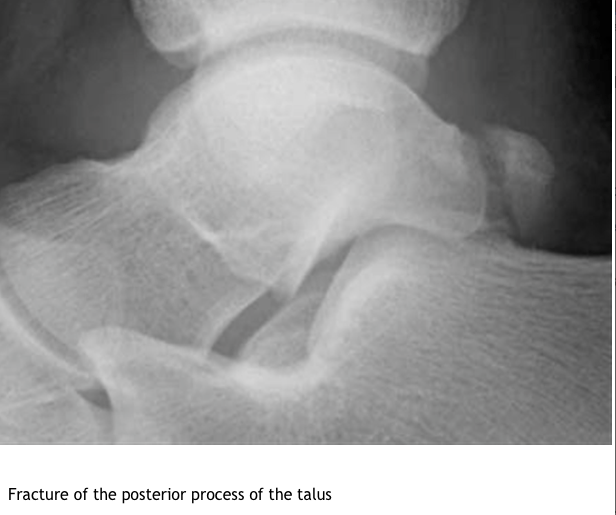

What is the Differential dx of Os trigonium ?

What is the Tx of Os trigonium?